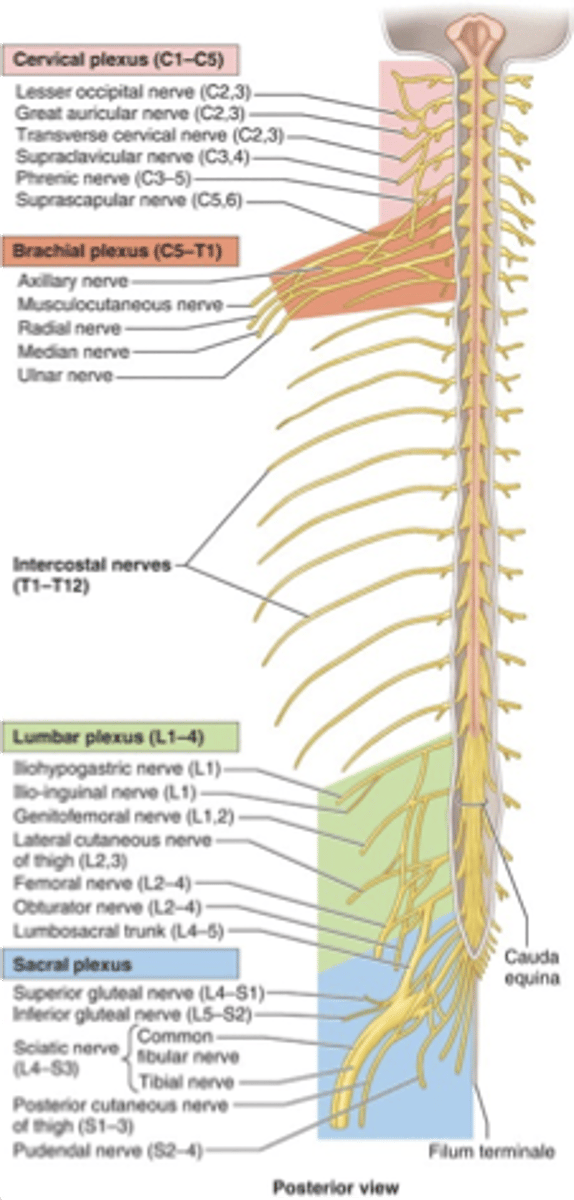

what are the 3 main spinal nerve plexuses?

1. cervical (C1-C4)

2. brachial (C5-T1)

3. lumbosacral (L1-S4)

spinal nerve plexuses are formed from merging (anterior/posterior) rami with one or more adjacent (anterior/posterior) rami. these multisegmental peripheral nerves are primarily involved in (facial/limb/visceral) innervation

anterior, anterior, limb